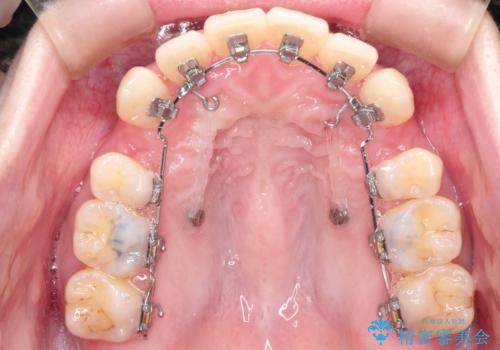

- 矯正装置

- ハーフリンガル

- 前歯が出ているため口が閉じにくく、横顔が気になるとのことで来院された患者様です。。

上下の前歯が前方に傾斜しており、口唇の突出感がありました。

上下左右の前から4番目の歯を抜歯して、上下の前歯を後方に移動させる計画としました。